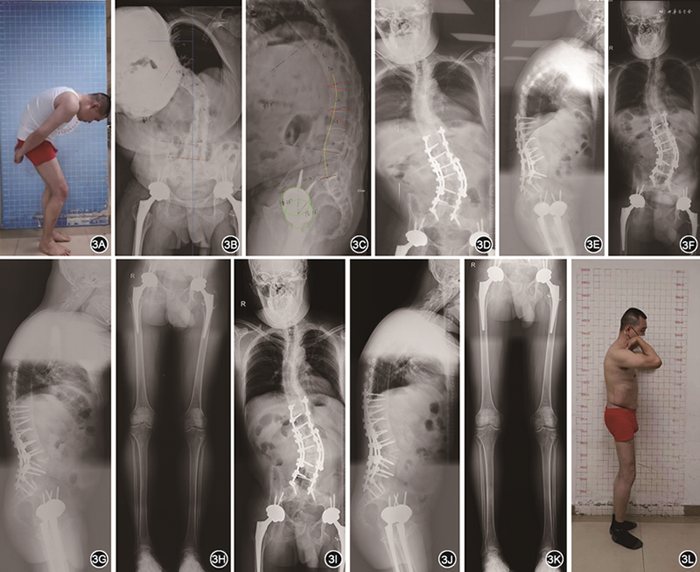

患者 男性,33岁,因“强直性脊柱炎20年,双侧髋关节强直、脊柱侧后凸10年”于2021年4月20日入院。患者13岁确诊强直性脊柱炎,10年前进展至以双侧髋关节屈曲位强直和脊柱侧后凸融合为特征的“剃刀背”畸形,并丧失竖直站立外观和双髋关节活动能力,行走能力严重受限,无法平视和仰卧。腰椎及双侧髋关节活动度丧失,双侧膝关节活动度0°~130°,双侧踝关节背伸20°,跖屈45°,行走时主要为双足跖跗关节和双踝关节屈伸活动。影像学检查:脊柱全长正、侧位片可见典型竹节样改变。冠状位、矢状位严重失平衡,顶椎位于L1~2椎间盘,上端椎位于T10,下端椎位于L4。骨盆前后位X线片示双侧骶髂关节间隙破坏(4级),骨盆极度后倾,双侧髋关节融合于屈曲45°,右侧外旋25°,左侧内旋30°(图1)。实验室检查:白细胞计数7.84×109/L,中性粒细胞百分比57.6%,血红蛋白161 g/L,C反应蛋白12.2 mg/L,红细胞沉降率2 mm/1 h,人类白细胞抗原B27(+),类风湿因子(-),抗核抗体谱(-)。诊断:强直性脊柱炎(终末期),脊柱侧凸后凸畸形并骨性融合,双侧髋关节破坏并骨性融合。